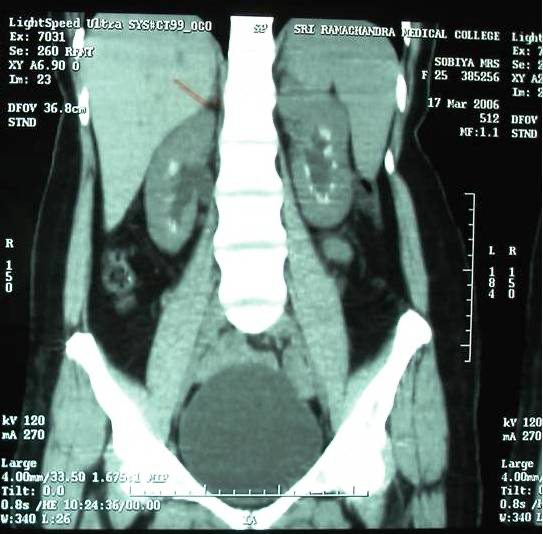

Further investigation for nephrocalcinosis revealed normal renal function and serum calcium levels, but she exhibited hypophosphatemia. Her iPTH levels were measured at 32 pg/mL, and arterial blood gases were within normal range. Metabolic analysis was conducted using a 24-hour urine sample, revealing hypercalciuria, hyperuricosuria, and reduced tubular reabsorption of phosphorus. Screening for aminoaciduria yielded negative results, and her oral glucose tolerance test was within normal limits. A 24-hour urine protein test showed levels of 278 mg, and her urine culture was sterile. Acid loading test, conducted with ammonium chloride to exclude renal tubular acidosis, indicated normal urinary acidification. An abdominal computerized tomographic scan identified nephrocalcinosis and mild splenomegaly.